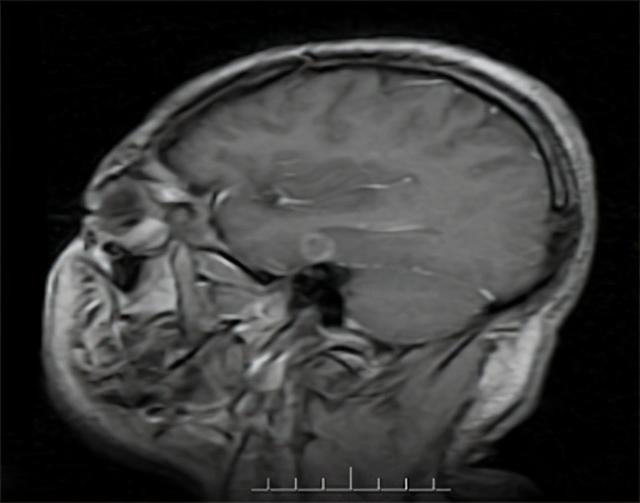

4、头部MRI/CT

可能会经常表现出脑菱缩、脑室增宽,以及基底节区异常信号,这样一般能够帮助诊断这种疾病。